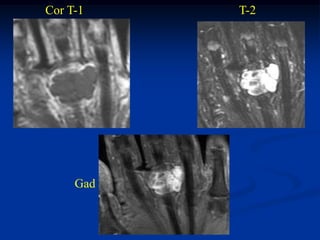

CLASSIC     Case #285         Sagittal T-1 MRI

67 year female with myxoid liposarcoma knee

Myxoid Liposarcoma The myxoid variant is the most common variant of the lipo- sarcoma and it is seen in a slightly younger age group between 40 and 50 years of age. It occurs in the lower extremities in 75% of cases, especially in the popliteal area. These lesions are slow growing and frequently asymptomatic in the early stages. On imaging studies, the MRI is the best method for visualizing these tumors that will have a mixed high and low signal on the T-1 weighted image because of the high percentage of fatty tissue in the tumor. Histologically, there will be evidence of malignant lipoblasts and it is common to find a plexiform network of small capillary tubes running thru the fatty tumor, similar to the capillary hemangioma. The prognosis for this variant is quite good after a wide local surgical resection, followed in most cases by local radiation therapy. The chance of pulmonary metastases runs as high as 20% and occasionally there will be multifocal myxoid

liposarcomas occurring inthe extremities as well as in retro- peritoneal locations. Occasionally, one will see a transitional form of myxoid converting into a higher grade round cell lipo- sarcoma which carries a more guarded prognosis.

CLASSIC Case #285 Sagittal T-1 MRI 67 year female with myxoid liposarcoma knee